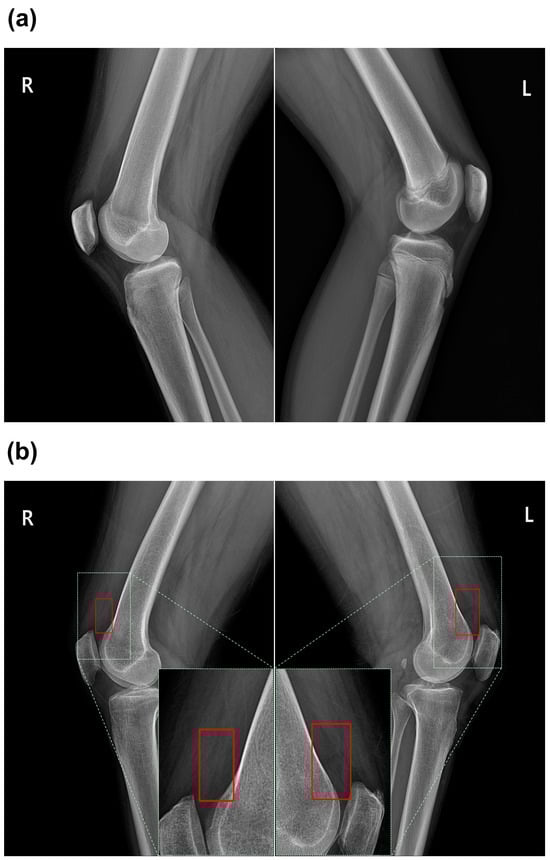

2.3.1. Knee Structure-Aware Image Preprocessing